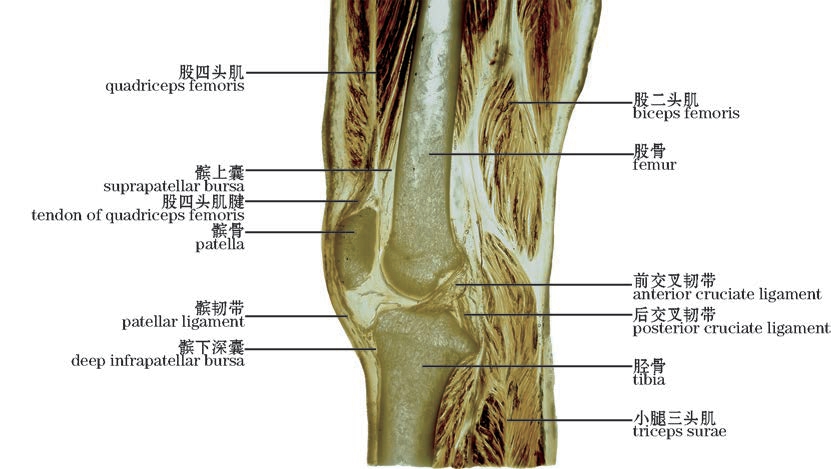

图2-48(1) 膝关节矢状切面—1

The knee joint.Sagittal section—1

img

图2-48(2) 膝关节矢状切面—2(外侧面观,左)

The knee joint.Sagittal section—2(Lateral view,left)